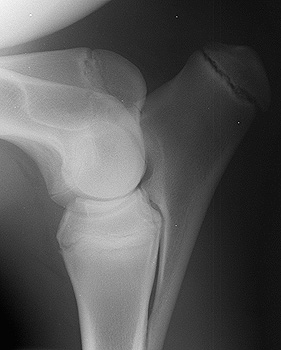

Radiograph of the Right Lateral View - Right Elbow

Figure 1: Right lateral view - right elbow